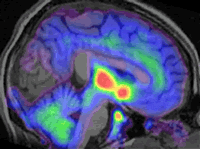

De interés fue el hallazgo de la activación de la corteza frontal dorso lateral después de la administración de placebo, ya que esta región es importante en la modulación cognitiva del dolor .En una investigación complementaria , Jon-Kar Zubieta de la Universidad de Michigan utilizó un trazador radioactivo que le permitió visualizar los receptores cerebrales para opiáceos con el PET scan, que se hicieron aparentes después de la administración tanto de opiáceos como de placebo en un grupo de catorce voluntarios sanos (Figura 1).

En otras palabras, el placebo actúa a nivel de las mismas regiones del cerebro “dedicadas” al dolor y lo hace por medio de opiáceos cerebrales naturales o endógenos.

| Figura 1: Receptores de los opiodes ocupados por endorfinas inducidas por el placebo y visualizados por medio de moléculas radioactivas (PET SCAN). | Figura 2: La intersección de las líneas incide sobre el área anterior de la circunvolución del cíngulo .Los sujetos investigados pudieron aumentar o disminuir la actividad sobre esta región voluntariamente por medio de observación directa, alterando la percepción dolorígena (fMRI). |